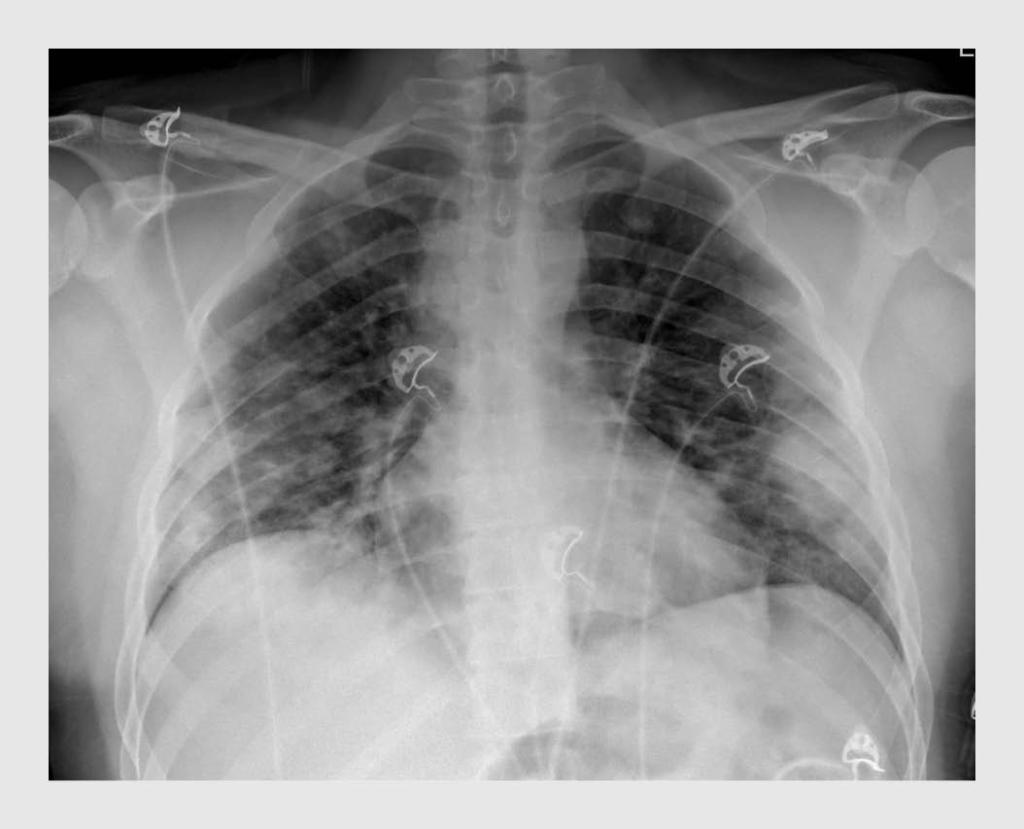

Figuur 1

Thoraxfoto van patiënt B

Deze patiënt was na 2 weken met klachten passend bij covid-19 toenemend kortademig geworden

De X-thorax laat bilateraal consolidatieve longafwijkingen zien, zoals frequent wordt gezien bij patiënten met covid-19.